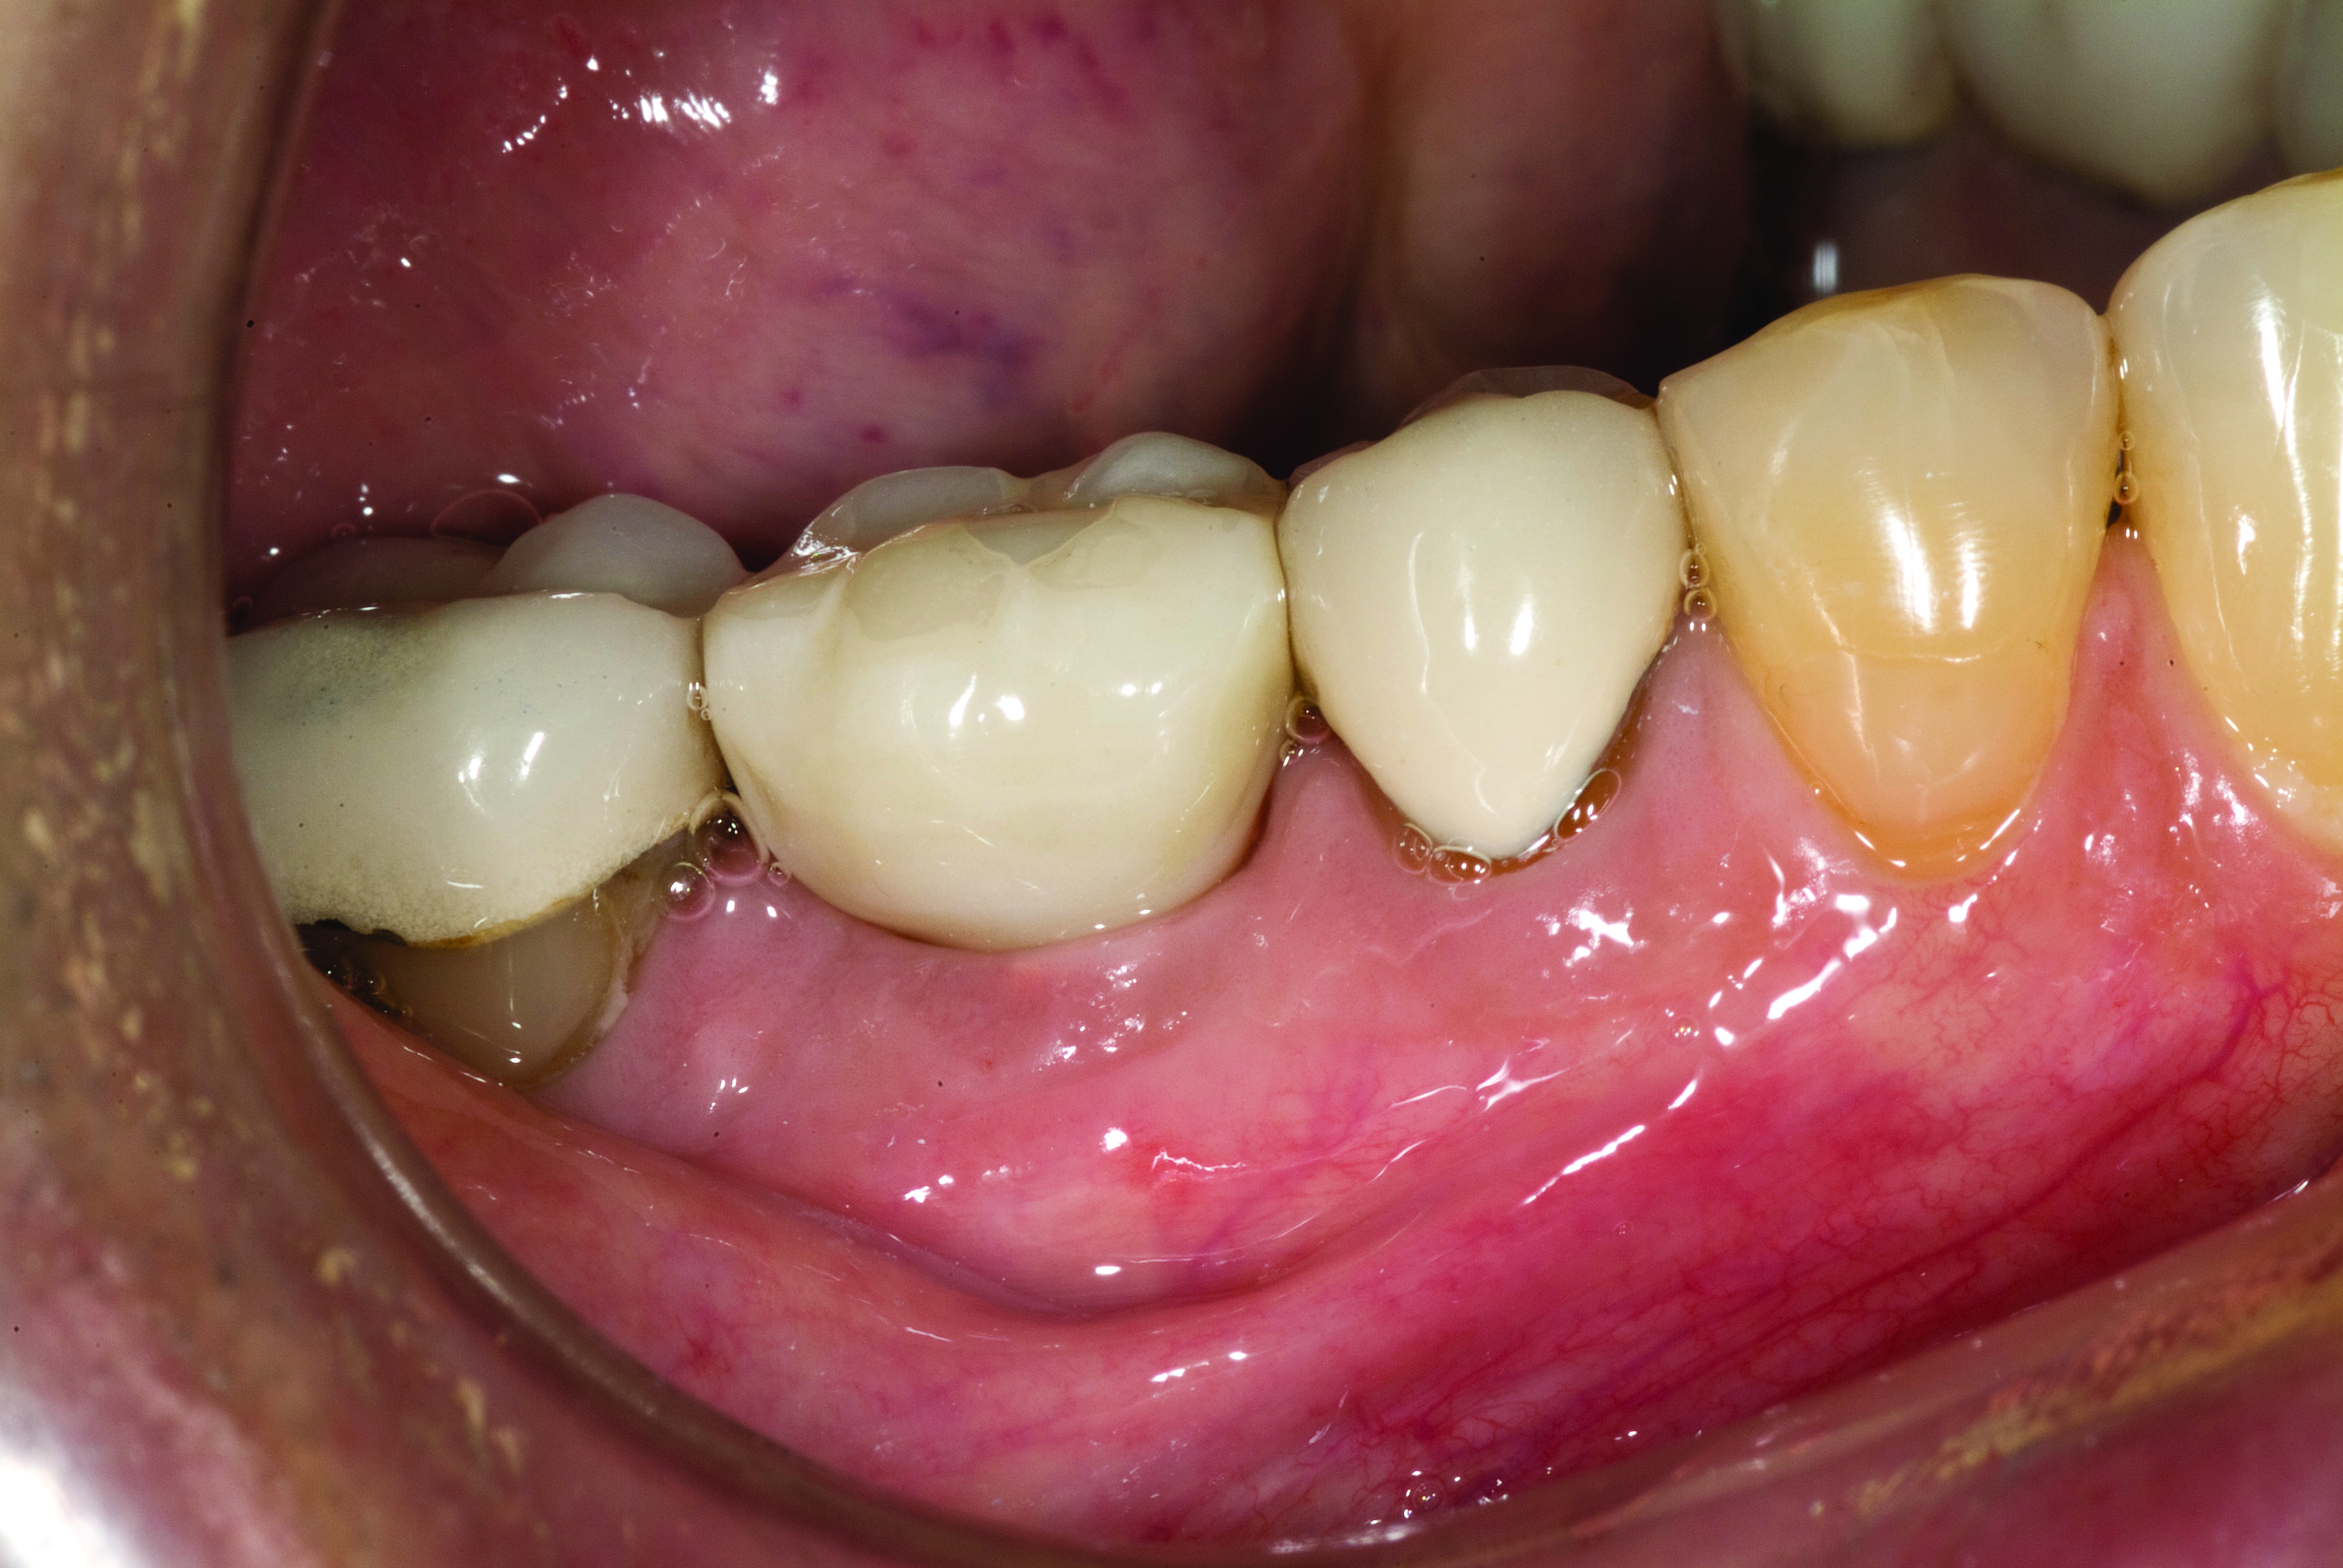

Fig 3. Confirmation of seating of scan body.

Figure 3

A mandibular right first molar was extracted due to an advanced Class III furcation and an irreversible pulpitis—a combination lesion. An immediate implant placement protocol was elected, and a PEEK abutment was placed on the implant (Figure 1). After 3 months of healing, a scan body was placed on the osseointegrated implant (Figure 2 and Figure 3), and an intraoral scan was taken (TRIOS Pod) (Figure 4) for the fabrication of a screw-retained crown.